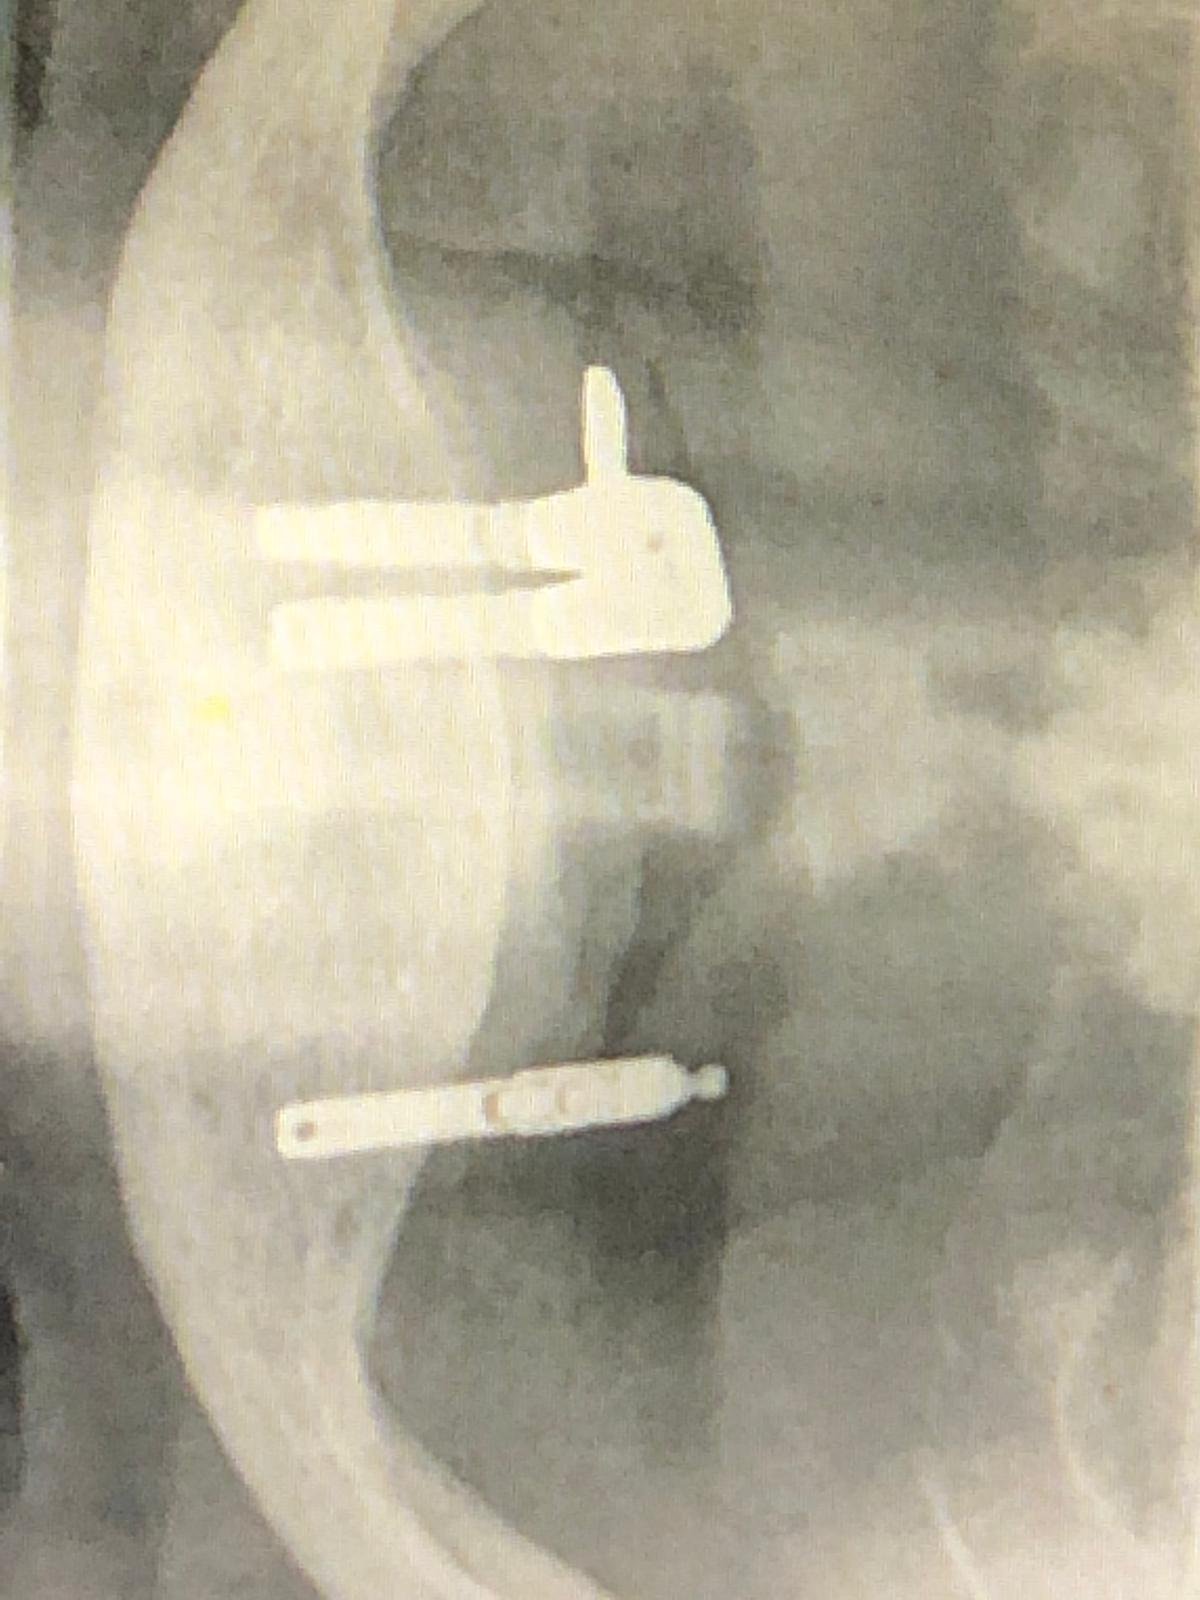

Buenos días! Me podéis ayudar con la marca de estos IOI puestos hace unos 20 años?! Gracias !!

Sabéis que implantes son?Muchas gracias!!

Buenas. Sabriais que implantes son estos? Necesito cambiarles el tornillo, y no se cuales son. Muchas Gracias!